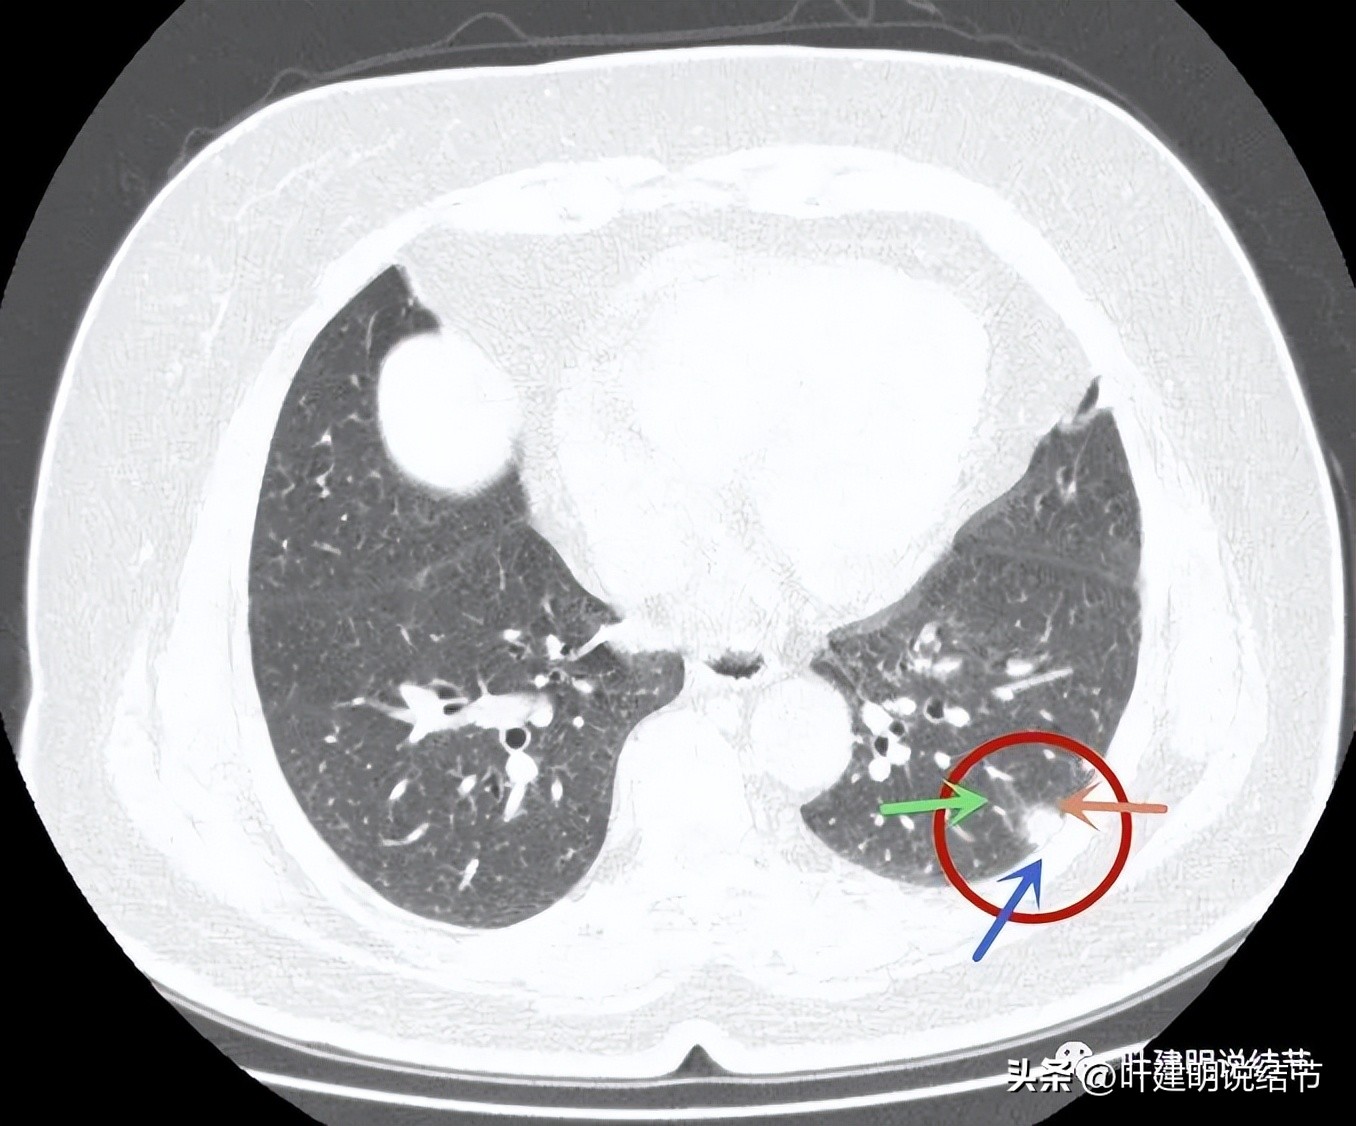

近肺门侧斑片影,胸膜距离近但没有牵拉;表面似乎有晕(砖色箭头)。

病灶不是很致密,中间有些偏低密度的成分,胸膜间隙征明显(按理这是肿瘤的特点,说明水肿不明显。但实性的,为什么没有牵拉?要么会是粘液腺癌吗?但粘液腺癌应该密度更均匀密实一些)。

病灶有血管进入,但血管是逐渐变细的,不是异常增粗。而且病灶的几条边都比较平直,缺乏膨胀性。与胸壁也是紧贴,没有造成牵拉或侵犯影响。

边缘平直,血管进入变细